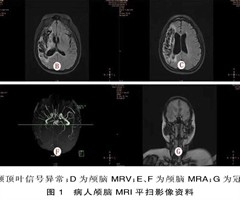

脑微出血及白质高信号与缺血性脑卒中病人机械取栓术后造影剂外渗的关系

摘要 目的: 探讨急性前循环缺血性脑卒中机械取栓术后造影剂外渗的影响因素,分析其是否与脑白质高信号及微出血相关。 方法: 回顾性分析2020年1月—2021年11月入住郑州大学附属洛阳中心医院神经内科行机械取栓的急性前循环缺血性脑卒中病人6...